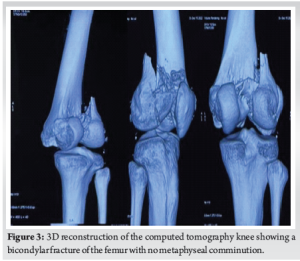

A 25-year-old male presented to the emergency department with a history of a fall from a motorcycle following a road traffic accident. Following initial resuscitation, plain radiographs of the knee were obtained, revealing a distal femur fracture (Fig. 1). Due to the complex nature of the injury and suspected intra-articular involvement, a computed tomography (CT) scan of the knee with 3D reconstruction was performed. It revealed isolated coronal fractures of both femoral condyles, confirming the diagnosis of a double Hoffa fracture (Fig. 2 and 3). Both the fracture fragments were separated, with no bony bridge connecting the two. The fracture was classified as AO 33-B3. After appropriate pre-operative planning and preparation, the patient was taken up for surgery.